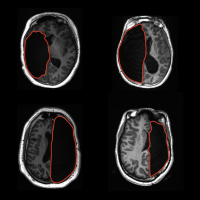

Top-down sectional views of 4 brain scans, showing missing hemispheres.

Word and face recognition can be adequately supported with half a brain, study finds

An unprecedented study of brain plasticity and visual perception found that people who, as children, had undergone surgery removing half of their brain correctly recognized differences between pairs of words or faces more than 80% of the time.